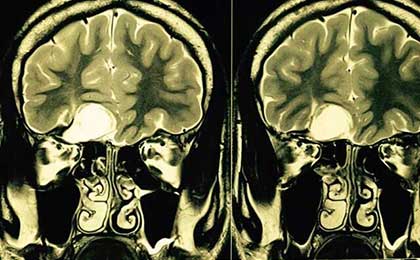

Huge Haemangioma PRE

• Huge Haemangioma PRE

Brainstem Glioma